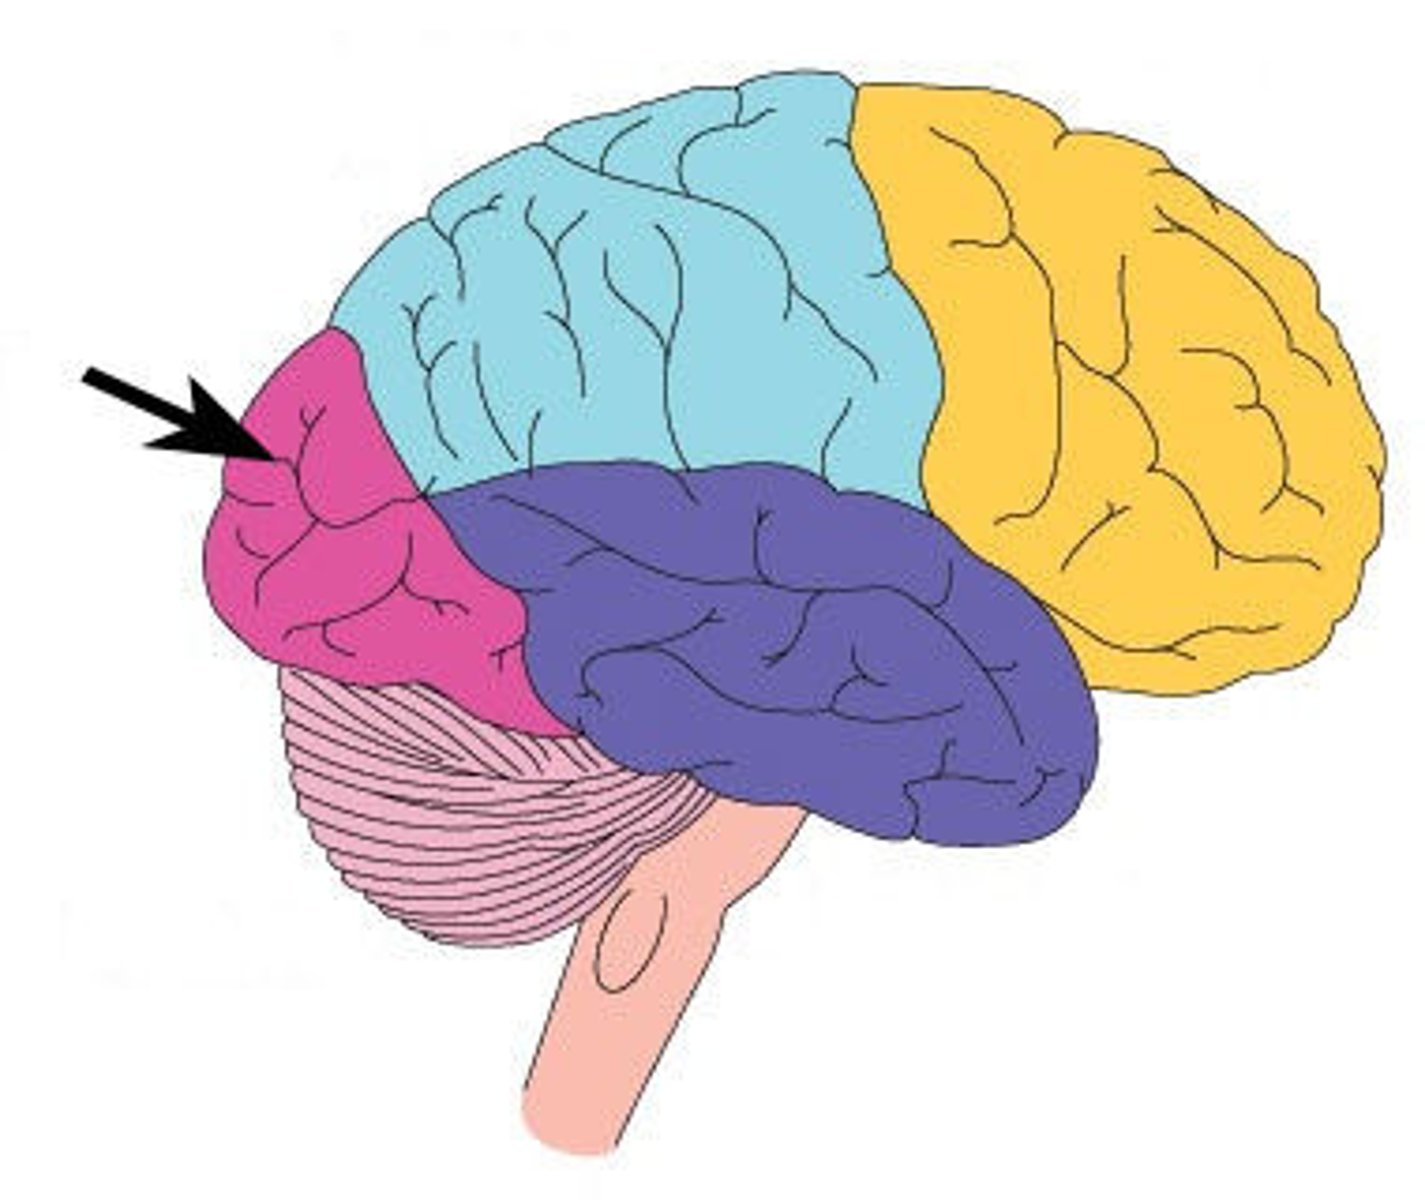

Frontal Lobe

What is this lobe?